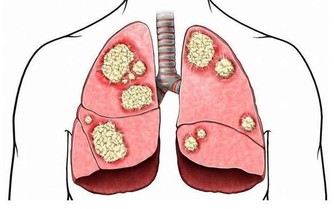

腸胃病科首席醫療顧問表示,大腸癌是我國第二癌症殺手,而華人則是患上大腸癌的最大群體。

腫瘤阻塞,當腫瘤長至相當體積,或浸潤腸壁肌層時,

可引起腸管狹窄,腸腔變小,腸內容通過受阻。